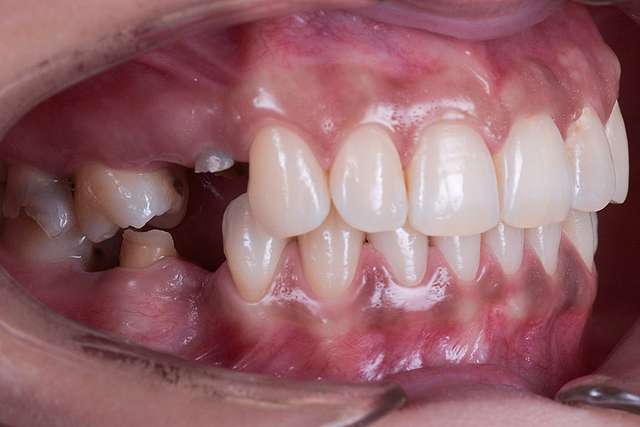

Guided surgery, for one, facilitates an ideal pre-planned position, in relation to available bone, and even more important, in relation to the future implant supported crown. Guided surgery translates into increased precision, which means safer surgeries, reduced surgery time, and reduced trauma. Also the focus of these types of treatments is shifted towards tissue reconstruction, which on the long run, has a far greater impact esthetically and biologically. Tissue stability means implant longevity. This case is a relevant example for this type of approach towards implant dentistry.